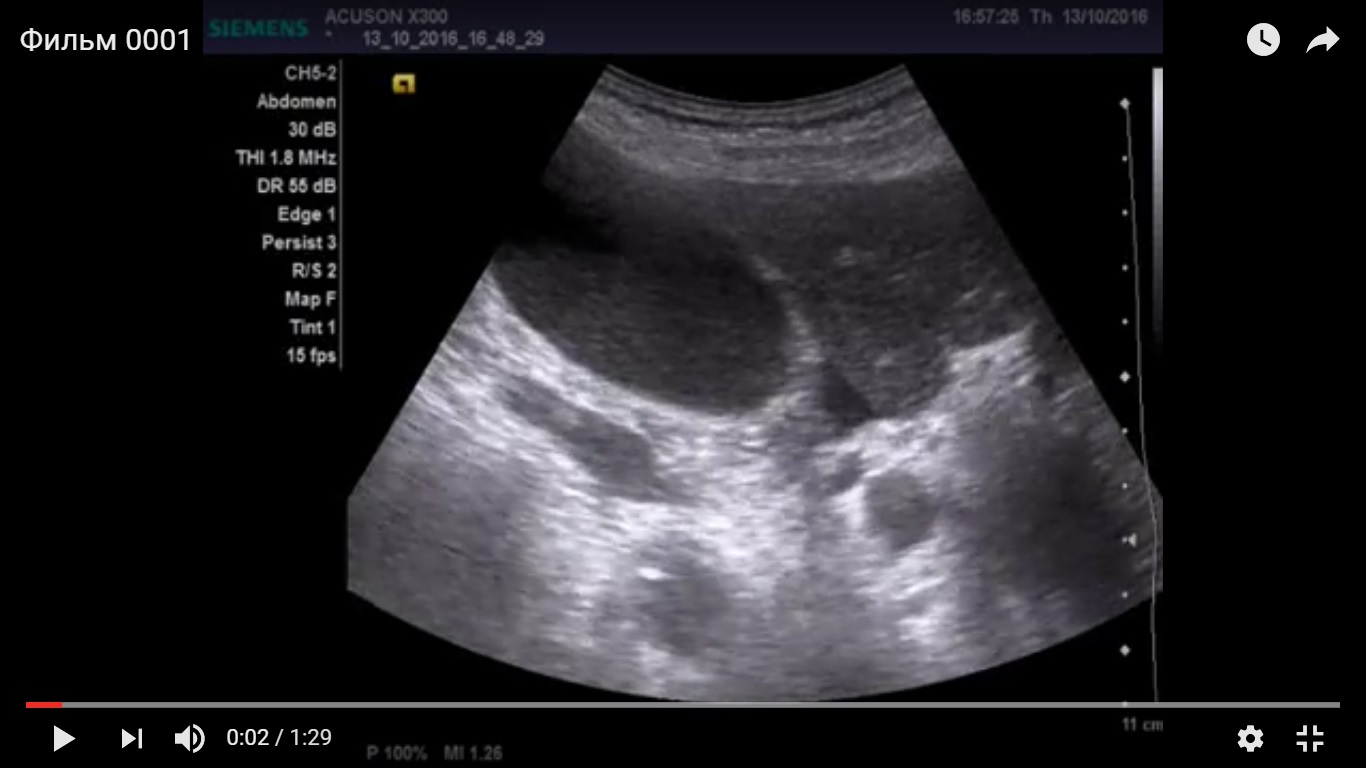

Дедушка лет 80, поступил по скорой с жалобами на боли в животе, провели узи, увидели выраженный асцит. Затем кто то видимо подсобрал анамнез, поставил катетер в мочевой и вывел 4 литра мочи. Для того что бы исключить хир. патологию и отправить дедушку на излечение в урологию повторно проведено уз исследование.

желчный пузырь увеличен 11*5 см, заполнен крупнодисперсной взвесью, в области шейки свободная жидкость. Дискинезия ЖВП?

Не видно причины гипертензии за уровне шейки ЖП -- холедоха, но признаки гипертензии есть.

есть признаки да. учитывая гемодинамически значимый стеноз ВБА, я бы склонился к эмпиеме пузыря, на фоне атеросклеротических изменений пузырной артерии. Учитывая возраст, клиника может быть стёрта, а учитывая наличие свободной жидкости, можно подумать о вялотекущей ишемии стенки и нарастающей деструкции. Я так бы рассудил.

Ишемический некроз стенки желчного пузыря теоретически может быть и он очень плохо диагностируется при УЗИ.

Но должны быть другие признаки воспаления, например, околопузырный инфильтрат и хоть какое-нибудь изменение стенок.

то что есть выложил. Хирурги сказали что клиники нет, перевели в урологию, но опыт показывает , что не всегда они правы. Считаю , что на узи не нормальная картина.